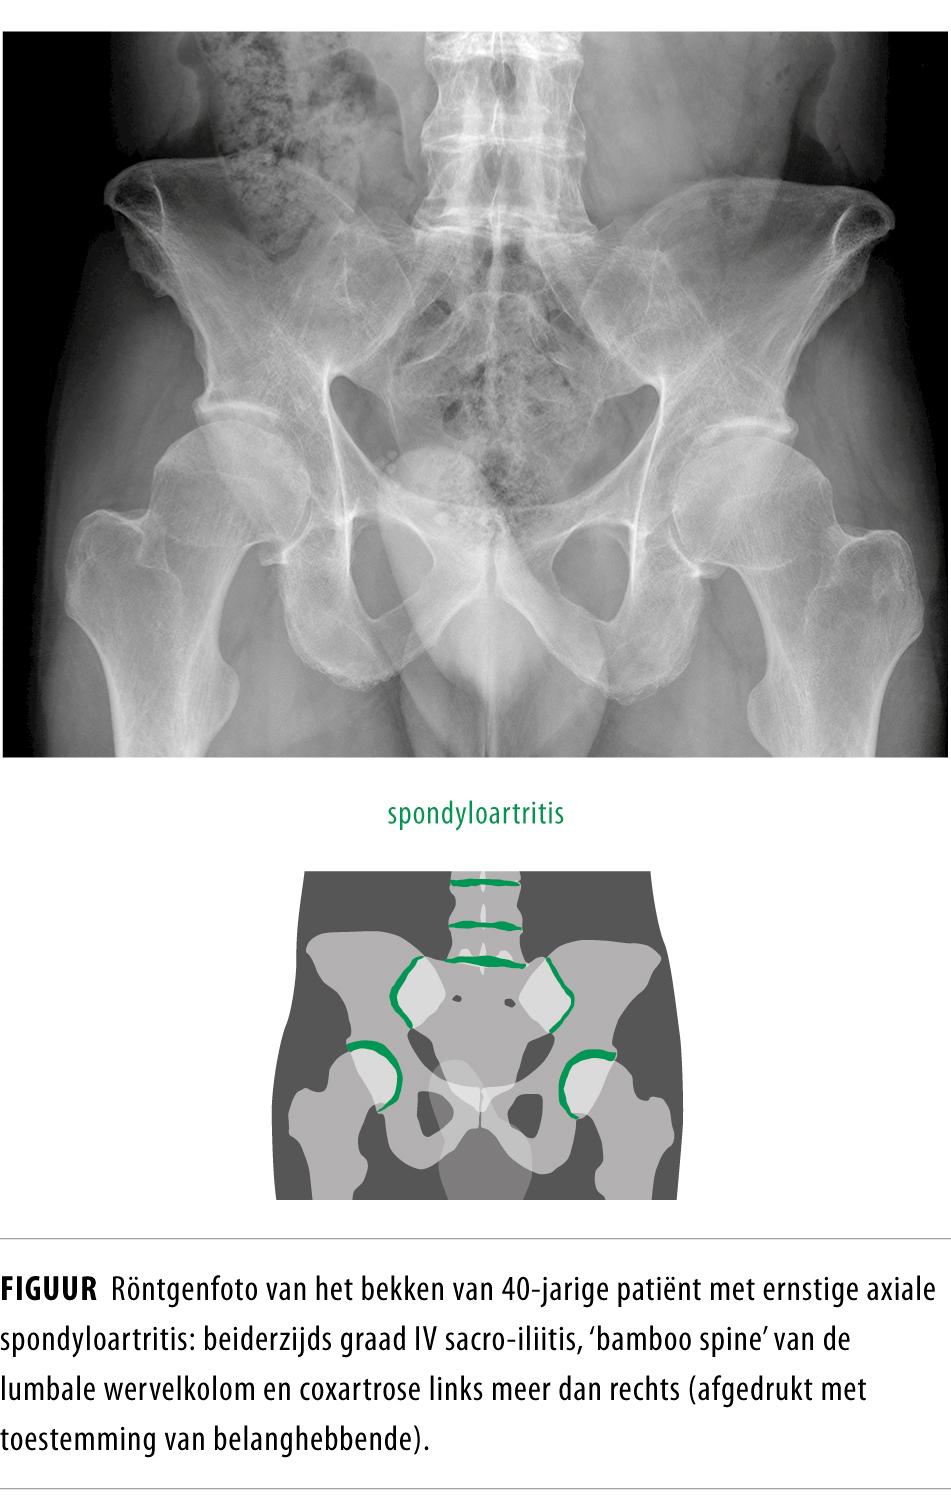

• Onder axiale spondyloartritis valt de bekende AS, maar ook een vorm van spondyloartritis die nog geen afwijkingen op de röntgenfoto laat zien, maar wel de symptomen en risicofactoren heeft die kenmerkend zijn voor axiale spondylartritis. Deze vorm wordt de non-radiografische axiale spondyloartritis genoemd.